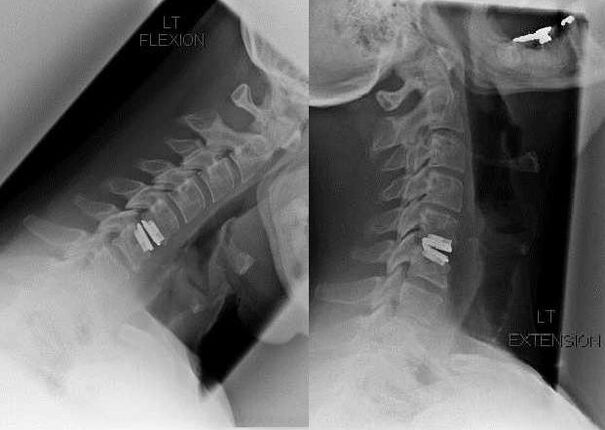

Le indicazioni per l'intervento chirurgico comprendono l'inefficacia del trattamento conservativo, nonché le complicanze dell'osteocondrosi cervicale, ad esempio la mielopatia discogenica, la sindrome dell'arteria vertebrale e la sindrome radicolare. Per decomprimere il midollo spinale, i vasi sanguigni e le radici spinali, vengono eseguite le seguenti operazioni:

Durante l’intervento chirurgico, i frammenti ossei e i legamenti possono essere asportati e i dischi intervertebrali possono essere rimossi completamente o parzialmente. Per le piccole sporgenze erniarie viene spesso eseguita la vaporizzazione laser del nucleo del disco.

Dopo l'escissione delle strutture vertebrali, la stabilizzazione dei segmenti di movimento spinale è spesso richiesta mediante fusione spinale o installazione di autoinnesti ossei e dermici.